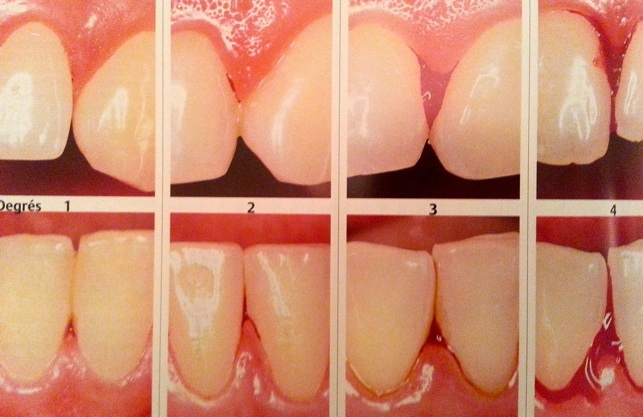

Résorption osseuse interradiculaire, classification des furcations: